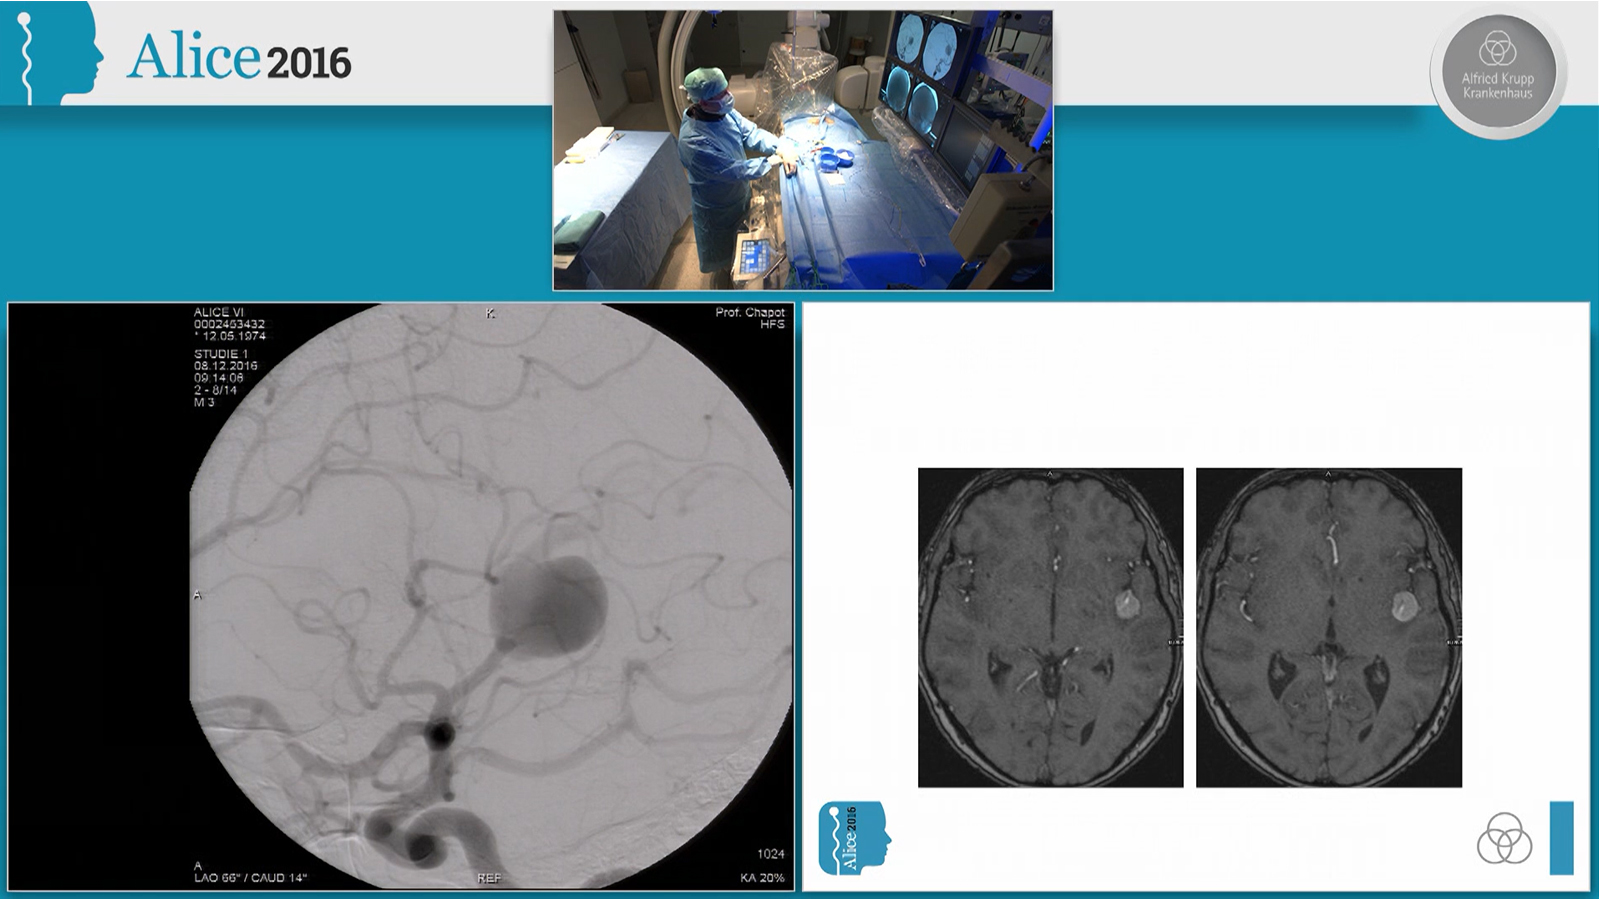

Ruptured hypothalamic AVM treated by transarterial embolization with PHIL